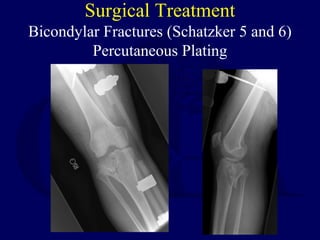

Surgical Treatment

Bicondylar Fractures (Schatzker 5 and 6)

Percutaneous Plating